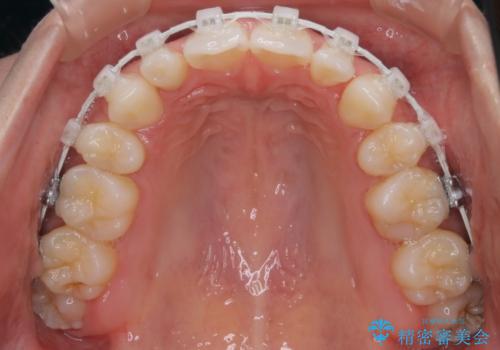

- 矯正装置

- 審美装置

- 口元をさげたいという主訴で来院されました。4番の歯を4本抜歯し、遠心移動とIPRをしました。右上2番が矮小歯のため見た目を重視するならクラウンの提案をしましたが、そのままでの治療を希望されました。

矯正治療の最終段階でスペースクローズにやや時間がかかりましたが、前歯が下がったことで口元の位置も下がりきれいになりました。